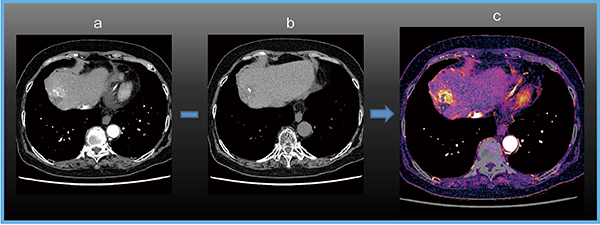

また,サブトラクションソフトウエアとして,“SURESubtraction Iodine Mapping”を使用している。これは,位置合わせのアルゴリズムに相互情報量を使った非線形位置合わせ法である。複数時相(単純相と造影相など)のボリュームデータに対して高精度の位置合わせが可能になり,サブトラクションボリュームデータが生成できる。このサブトラクションデータからヨードのみの情報を抽出したヨードマップを元の造影画像に加算することで,造影成分を強調する“CE Boost”画像を作成できる(図4)。

図4 造影成分を強調するCE Boost画像

a:造影CT b:単純CT(TACE後の肝細胞がん再発) c:CE Boost画像